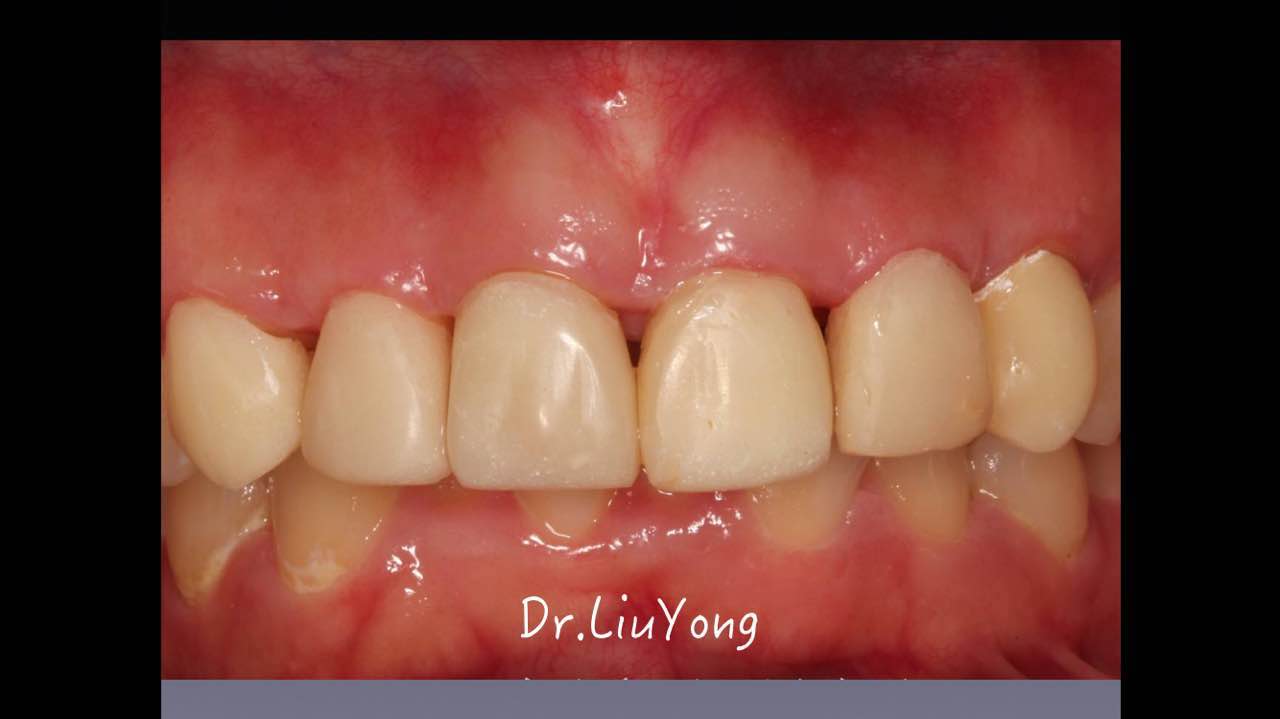

嚴(yán)重破壞生物學(xué)寬度,根尖瘺管,重行根管治療, 第一次冠延長建立唇腭側(cè)及鄰面BW,術(shù)后牙齦扇貝形差, 齦乳頭黑三角,再次行美學(xué)冠延長,建立牙齦扇貝形,手術(shù)免費, 患者因經(jīng)濟原因只能選擇鑄樁及鈷鉻合金烤瓷冠。終于完工